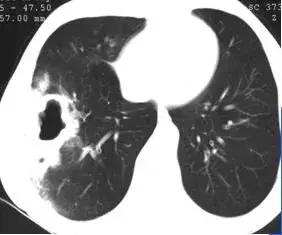

CT征象八:碎石路征

碎石路征(Crazy paving appearance):在HRCT上,表现为地图状分布的、重叠有网状的光滑细线影的磨玻璃影;最常见于肺泡蛋白沉着征。

细线影为小叶间隔水肿增厚,或蛋白样物质沉积于邻近小叶间隔的气腔内所致。

碎石路征(Crazy paving appearance)

碎石路征:肺泡蛋白沉着症(PAP)